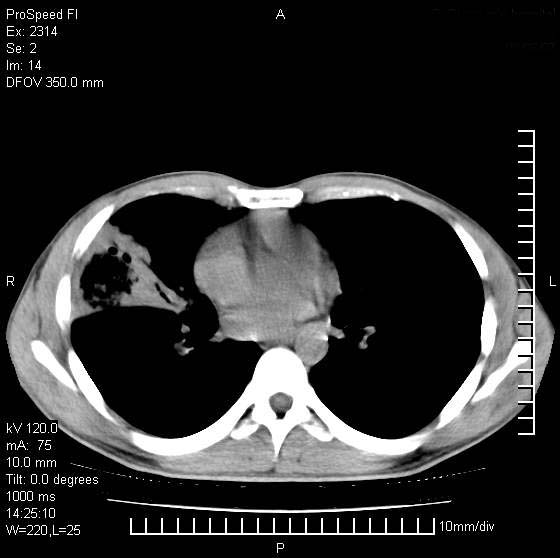

男性,再生障碍性贫血,入院前发热10天,最高40c,右侧胸痛,外院ct示右上,中肺边缘模糊的球性影(就是我现在图中标示的范围),考虑炎症,在我院使用头孢呋辛,洛美沙星10天,高烧消退,自感下午稍有发热,但今天ct示右上,中肺病灶明显扩大,还是考虑炎症,看其中的球型影是否霉菌感染??,是否能排除结核?

右肺中叶外侧段病变,上缘界限不清,下缘锐利,以段性发病为主,内见巨大空洞及空洞内容物,结合病史首先考虑:化脓性肺炎。不除外霉菌感染!

考虑霉菌感染.理由1\\有临床基础疾病,2\\有坏死的空腔,其内可见软组织影.

片状高密度影内见空洞影,内可见球形软组织密度影,并有新月征,考虑霉菌感染.